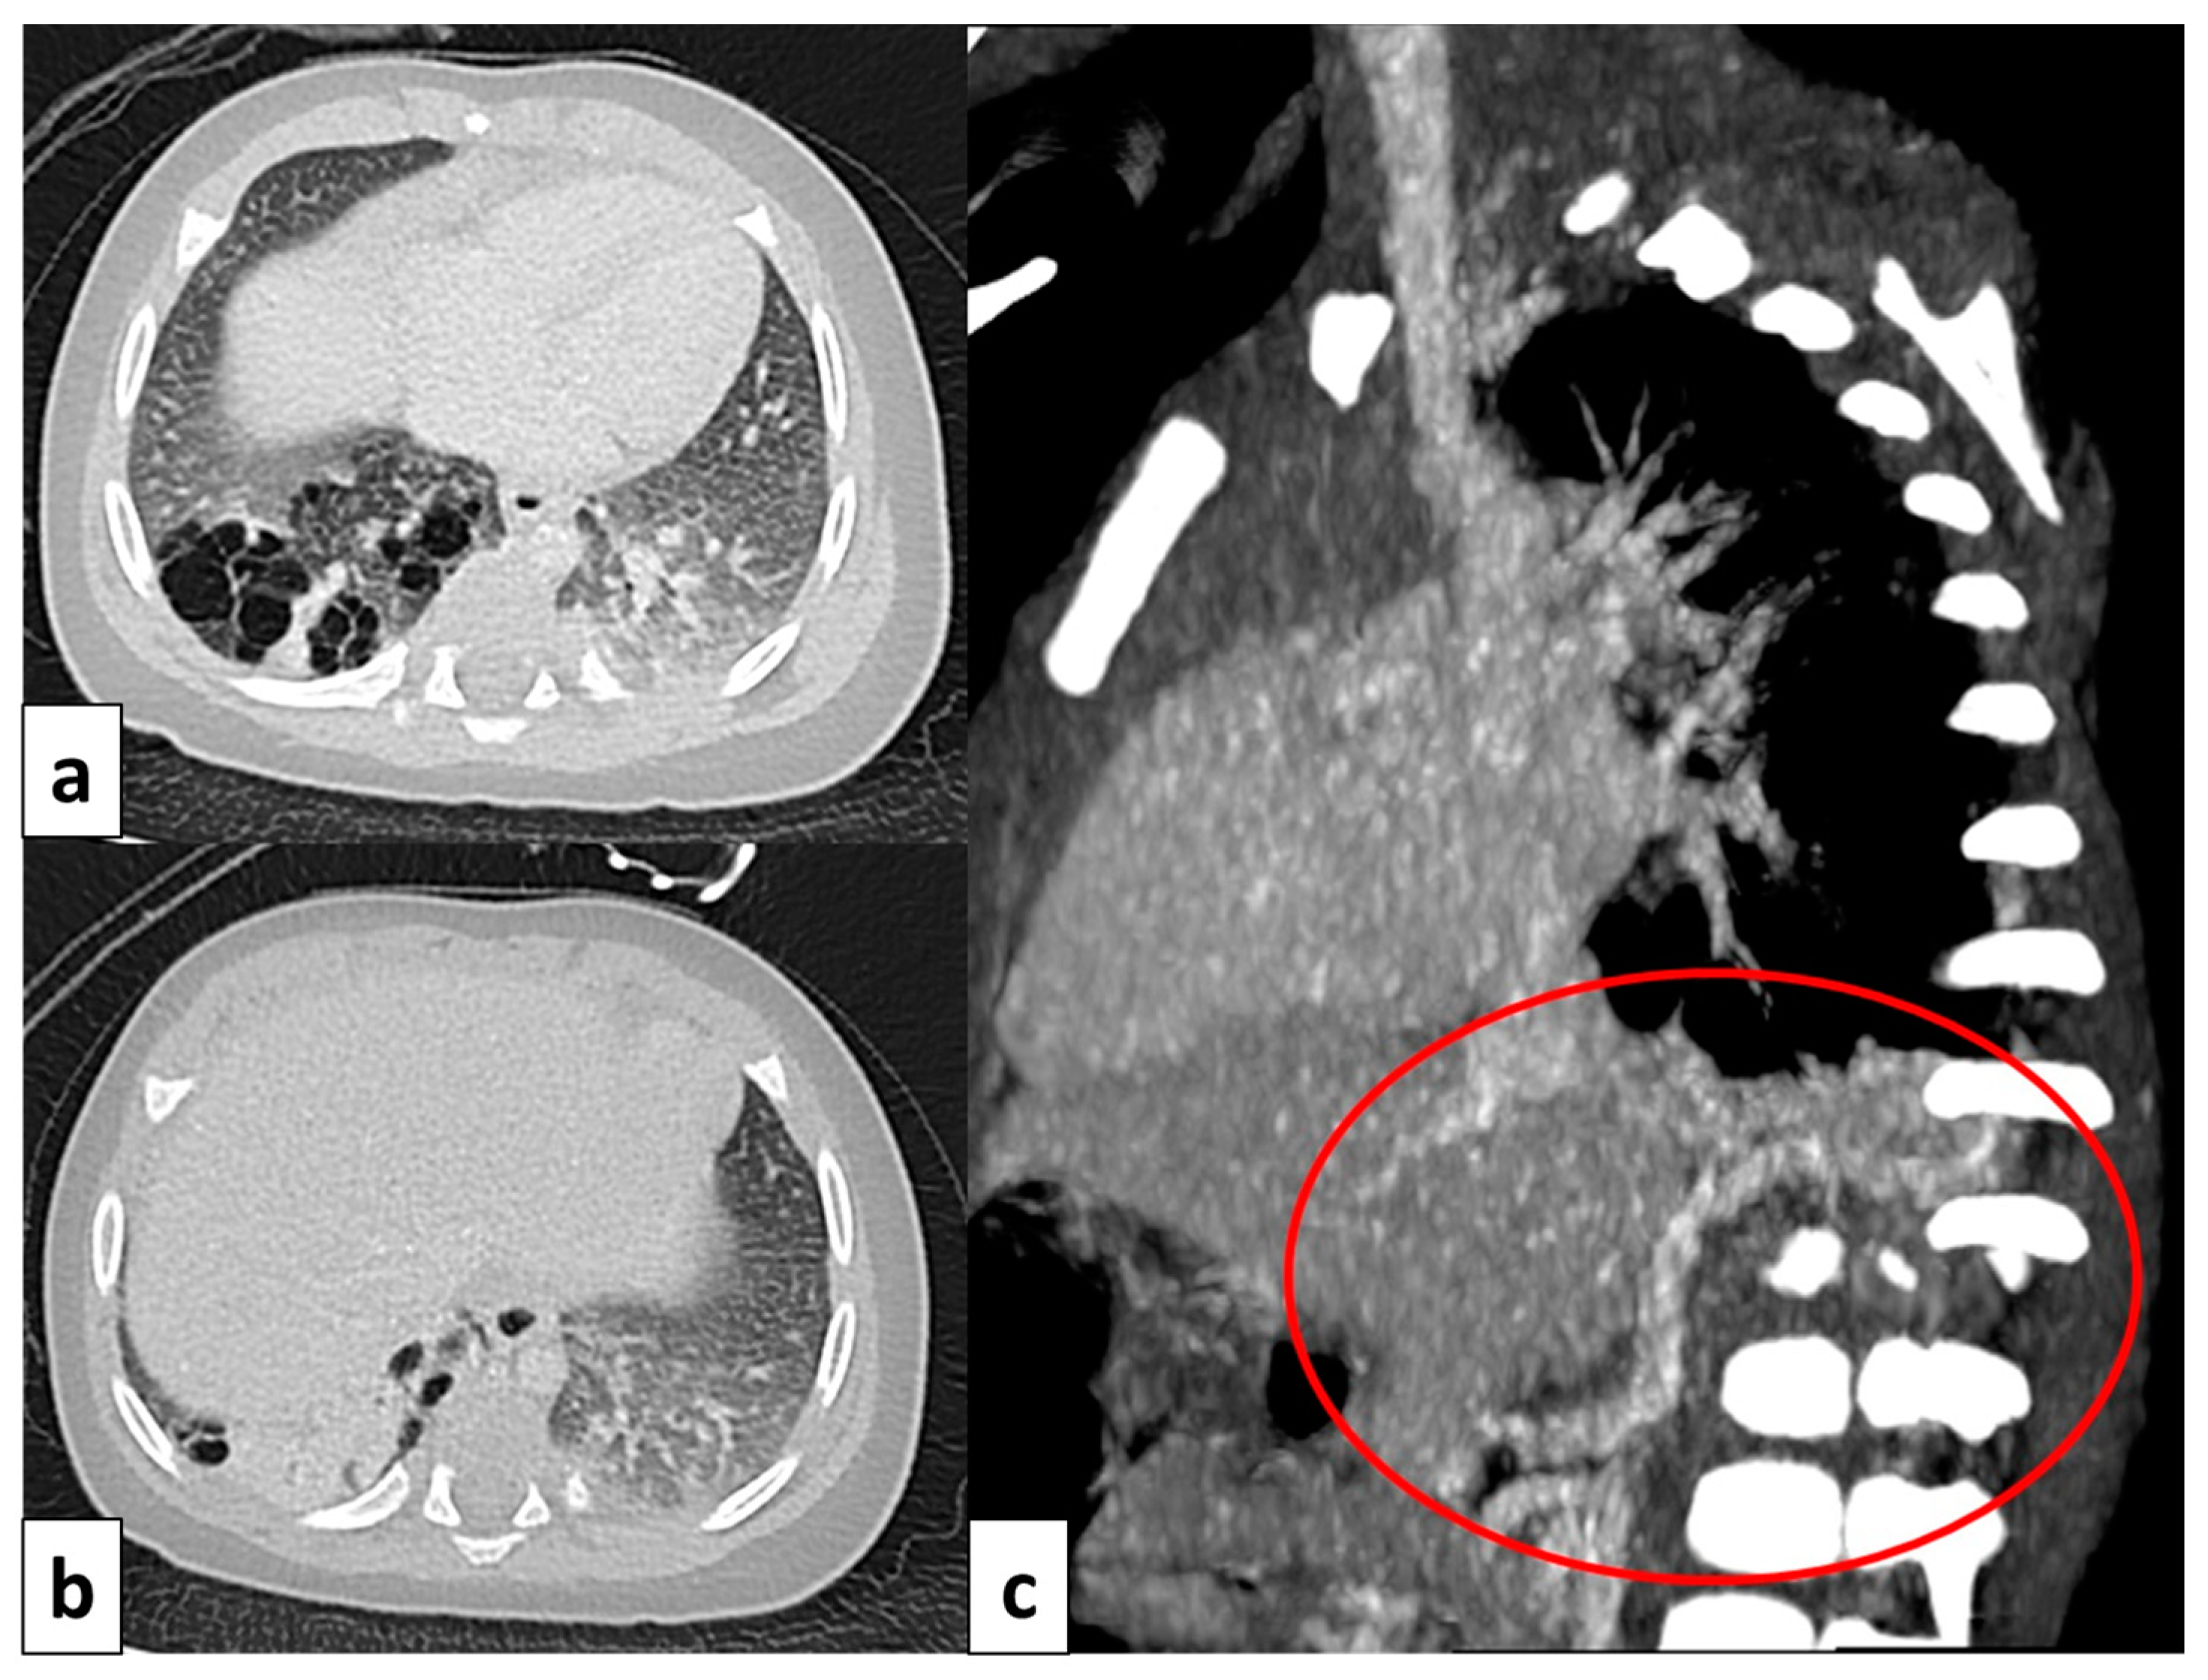

Figure 9.

CT image of a 4 month old girl presenting with multiple right cystic lesions <2 cm (a) compatible with CPAM type 2. Parenchymal consolidation (b) associated with the aberrant arterial (c) supply from the celiac trunk (red circle) and venous drainage into the pulmonary venous system, further evaluated with the coronal MiP reconstruction, represent a pulmonary intra-lobar sequestration. The combination of these findings supports the diagnosis of a hybrid lesion.